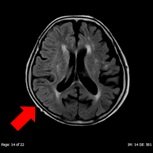

- 頭部MRI

| 頭部領域では、CT では分かりにくい脳梗塞や微小脳出血、脳腫瘍などの精査を目的とした撮影を行います。本検査では造影剤を用いることなく血管の描出をすることができ、血管狭窄、塞栓症などの診断にも有用です。病態によってはより詳しく調べるために造影剤を使用することもあります。 | ||

| DWI画像 | FLAIR画像 | MIP画像(血流途絶) |

| 心原性急性期脳梗塞 | ||